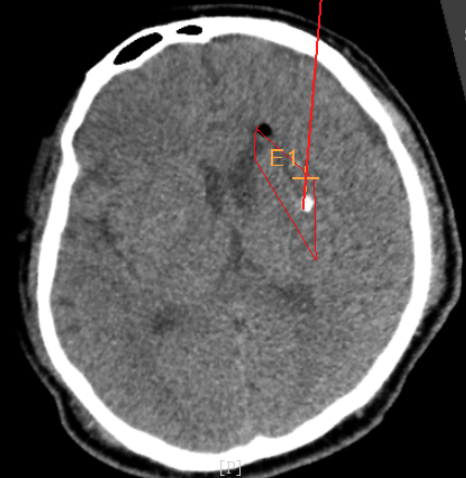

術(shù)前CT:血腫已經(jīng)液化,但仍有占位效應(yīng)

手術(shù)日當(dāng)天,醫(yī)生團(tuán)隊(duì)通過(guò)手術(shù)計(jì)劃系統(tǒng)為患者制定手術(shù)靶點(diǎn)及最安全的入顱路徑,隨后將手術(shù)規(guī)劃導(dǎo)入手術(shù)室的機(jī)器人當(dāng)中。

實(shí)際手術(shù)時(shí),機(jī)器人在幾分鐘內(nèi)就完成了空間注冊(cè),機(jī)械臂在定位儀的引導(dǎo)下自動(dòng)定位,準(zhǔn)確鎖定靶點(diǎn)。